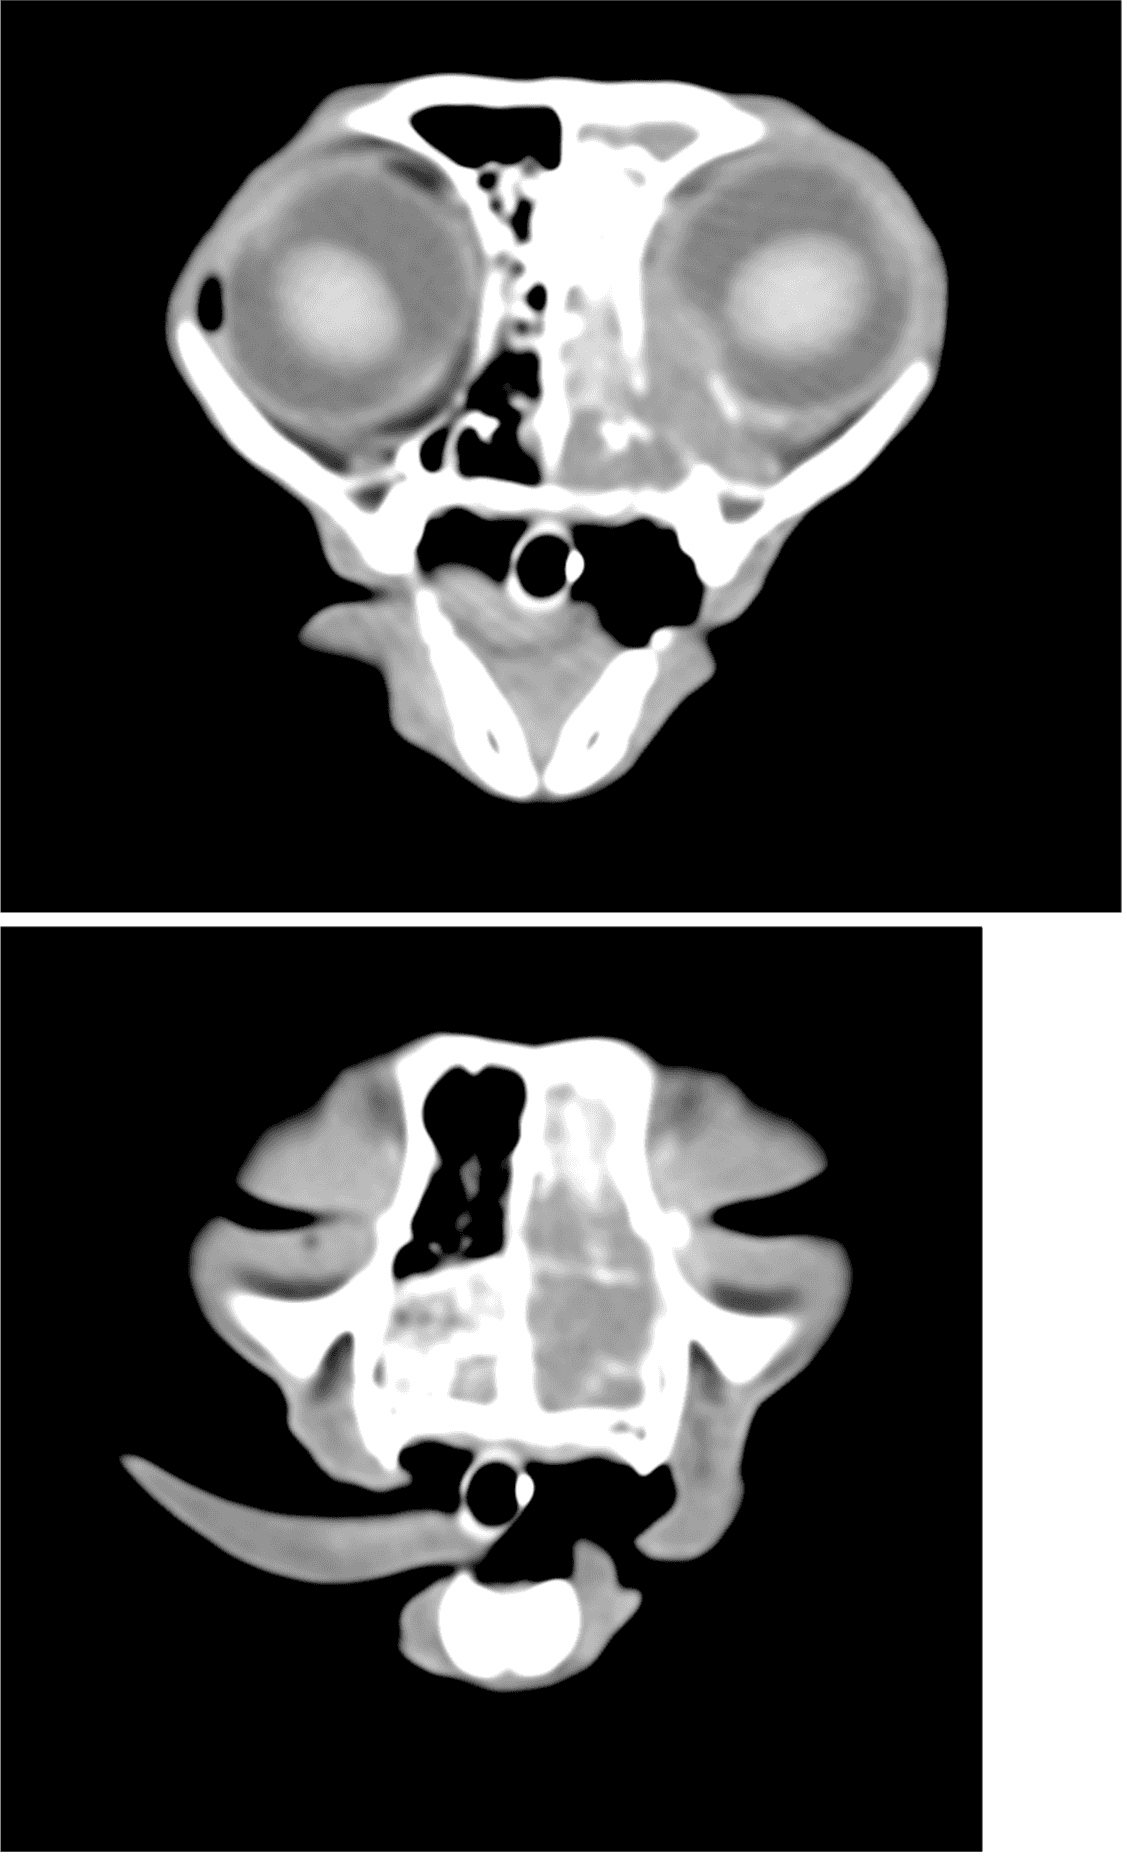

体重3.28kg(BCS3/5) 体温38.7℃ 心拍数160回/分 呼吸数28回/分 一般状態 :活動性100% 食欲100% 意識レベル 正常 一般身体検査 :左鼻より黄色鼻汁あり 左目の流涙あり 血液化学検査:特筆すべき異常所見なし 頭部CT(図1参照) 腹部超音波検査:左右腎臓の腎結石あり、その他諸臓器に特筆すべき異常所見なし

第5病日より放射線治療を実施した。照射プロトコルは1回8Gy 週1回 合計4回照射 総線量32Gyとなった 放射線治療の終了後、治療評価のためCT撮影を実施した。照射後CTでは大部分の病変は消失しているが、一部でびまん性病変の残存が疑われた。(図2)以上の所見より、放射線治療後残存したリンパ腫に対して化学療法を実施した。化学療法プロトコルは改変型COP療法とし、3ヵ月間継続した。治療後の経過は良好であり、現在化学療法終了から1年3ヵ月経過するが再発や転移は認められず、寛解を維持している。